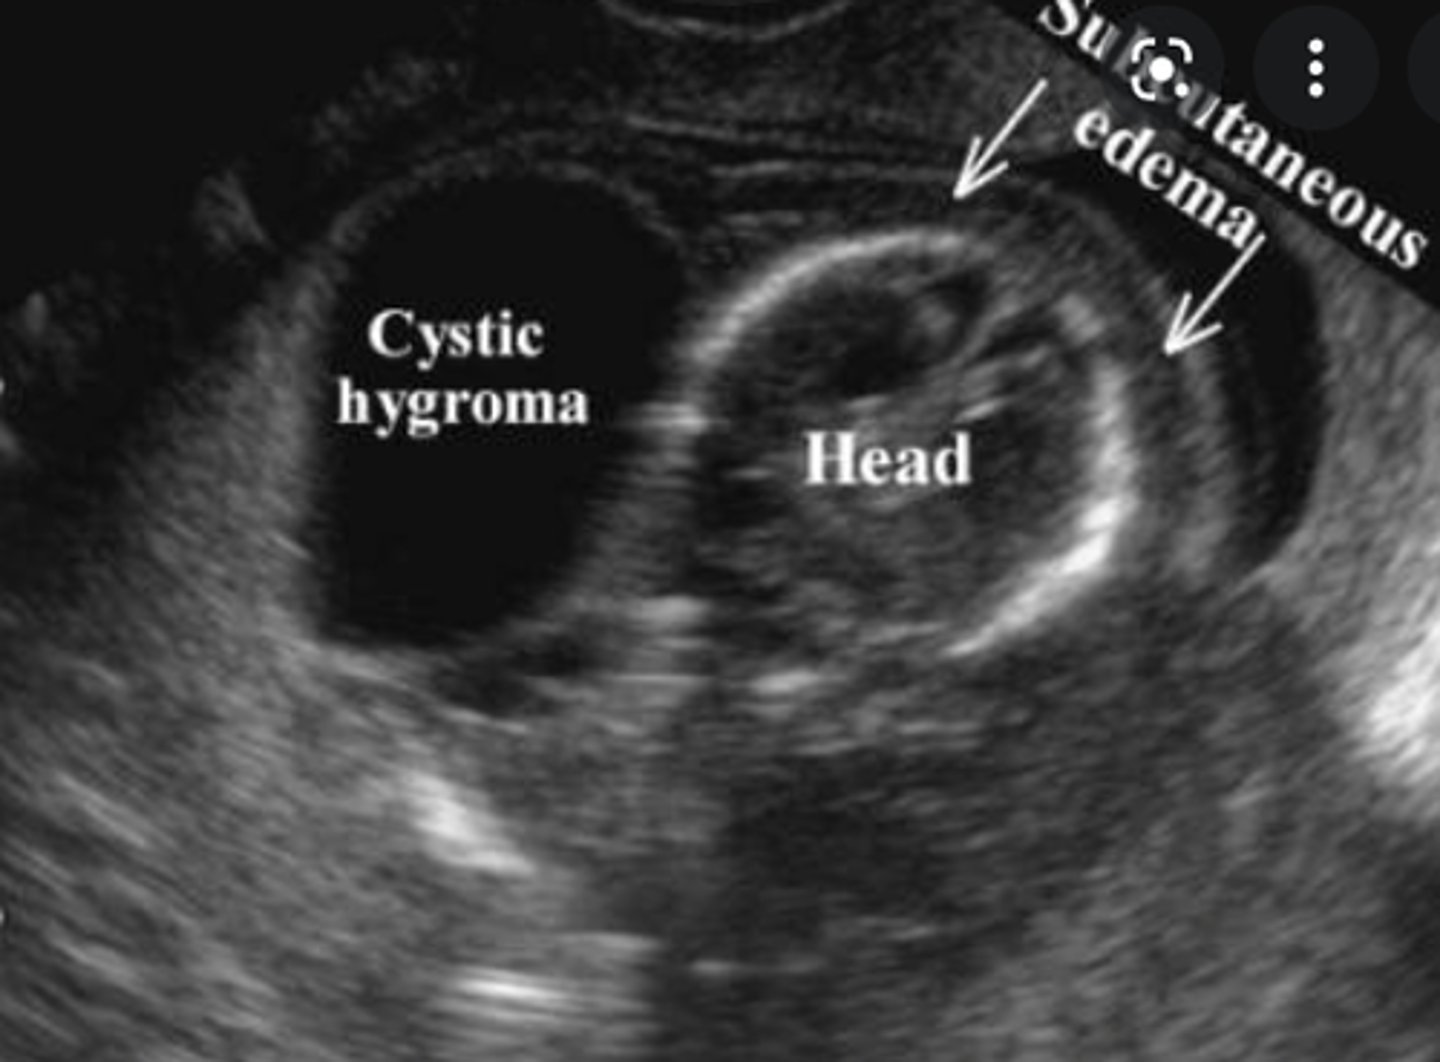

Cysts of the Neck - Cystic hygroma:

Etiology

-Inadequate drainage of lymph fluid into the _____

-Increased _____ from the epithelial lining

-Associated with _____ syndrome

Clinical findings

-Asymtpomatic

-_____ neck mass

Sonographic findings

-_____-walled, _____ cystic structure

-Inadequate drainage of lymph fluid into the jugular vein

-Increased secretion from the epithelial lining

-Associated with Turners syndrome

-Posterior neck mass

-Thin-walled, multilocular cystic structure